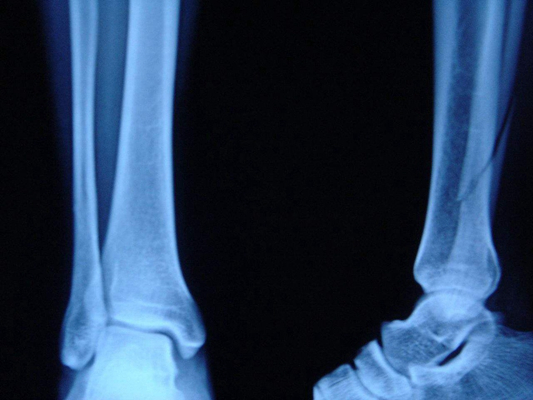

骨折圖片